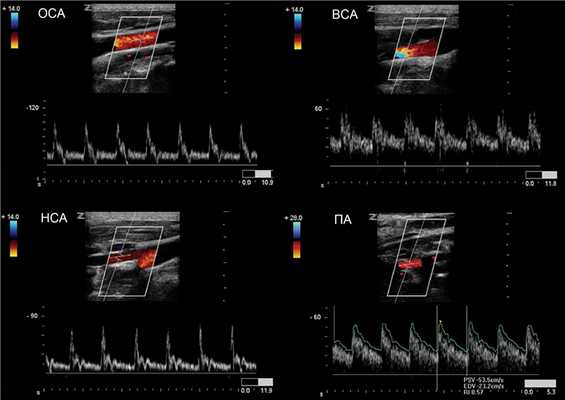

Оценка мозгового кровотока включает брахиоцефальные артерии на уровне шеи и интракраниальные сосуды головного мозга.

В В-режиме и ЦДК сканируют ОСА до бифуркации; выше бифуркации исследуют НСА через передний доступ, ВСА через боковой доступ.

Оценивают дистальный отдел ПГС, ПКА, ОСА на всем протяжении, ВСА от устья до входа в череп, НСА в начальном сегменте, ПА в сегментах V1 и V2.

Спектр ОСА имеет резкий подъем и узкий пик в систолу, низкий поток в диастолу, дикротический вырез в поздней систоле и ранней диастоле.

Cпектр НСА похож на ОСА, иногда ретроградный поток в диастолу, звук «стреляющий». Постучите по поверхностной височной артерии, увидите Т-волны на спектре НСА.

Спектр ВСА имеет постепенный подъем и широкий пик в систолу, высокий антеградный поток в диастолу, пульсация почти отсутствует, звук «дующий».

Спектр II сегмента ПА по форме похож на ВСА, Vps и Ved в 1,5 раза ниже, поток исключительно антеградный. Vps может снижаться на верхних отрезках, но не более 20%.

В ОСА и НСА высокое сопротивление, низкий поток в диастолу; в ВСА и ПА низкое сопротивление, высокий поток в диастолу.

Скорости кровотока и индексы сравнивают с нормальными значениями. На сосудах обеих сторон асимметрия Vps не должна превышать 20%, индексов RI и PI — 10%.